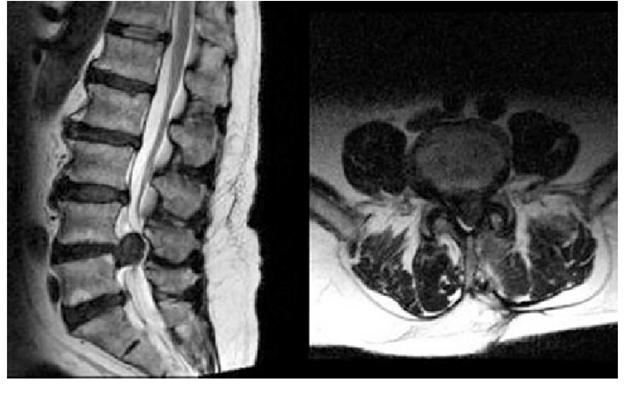

Hérnia de Disco Lombar

Coluna Lombar

Hérnia de Disco Lombar: aspectos clínicos, diagnóstico e tratamento

Uma análise clínica completa sobre a hérnia de disco lombar: como identificar o nível afetado, quais exames pedir e quando indicar cirurgia.